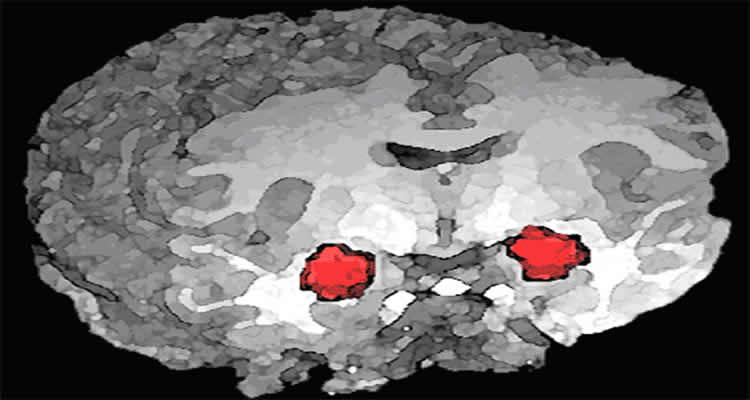

Activating the brain’s amygdala, an almond-shaped mass that processes emotions, can create an addictive, intense desire for sugary foods, a new U-M study found.

In the study, whenever the rats pushed a lever to earn a particular sugary reward, a laser light painlessly activated the amygdala in their brains for a few seconds, making neurons in it fire more excitedly. Their amygdala was never activated when the rats earned an identical sugary reward by pressing a separate lever.

Then, a simultaneous opportunity to earn both sugary rewards was given. Faced with a choice, the rats focused only on earning the particular sugary reward that had previously excited their amygdala, while completely ignoring the other.

The rats also were willing to work much harder to earn the sweet reward associated with amygdala activation than to earn the other sweet reward.

The amygdala activation focused the rats’ desire on the sweet reward with which it was associated. By itself, the amygdala-stimulating laser appeared worthless to the rats, which didn’t seem to care if the amygdala-stimulation was on or off, unless the sugary reward was also present.

Robinson said the results suggest a role for the amygdala in generating focused and almost exclusive desire as seen in addiction.

Image Source: The image is credited to the NIH. The image has been released into the public domain